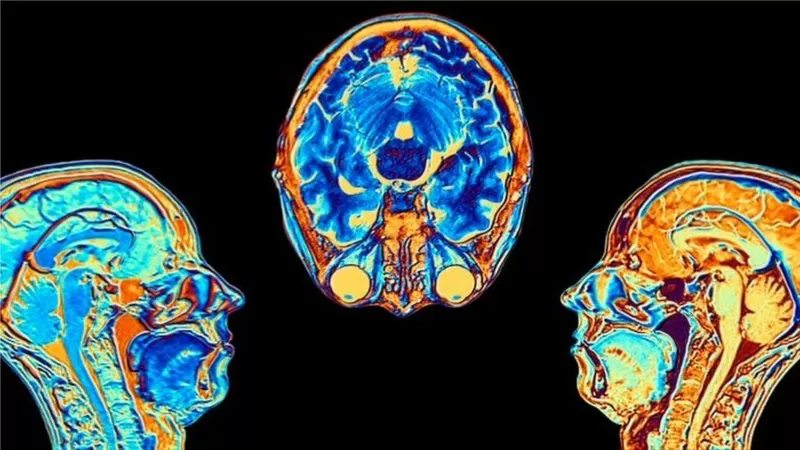

Contagiarse de covid-19 puede provocar cambios en el cerebro, según indicó un estudio publicado en la revista Nature.

Los investigadores hallaron diferencias significativas en las resonancias magnéticas hechas antes y después de la infección.

Incluso después de una infección leve, las imágenes mostraron que el tamaño total del cerebro se había reducido ligeramente, con menos materia gris en las regiones relacionadas con el olfato y la memoria.

FUENTE DE LA IMAGEN,GETTY IMAGES